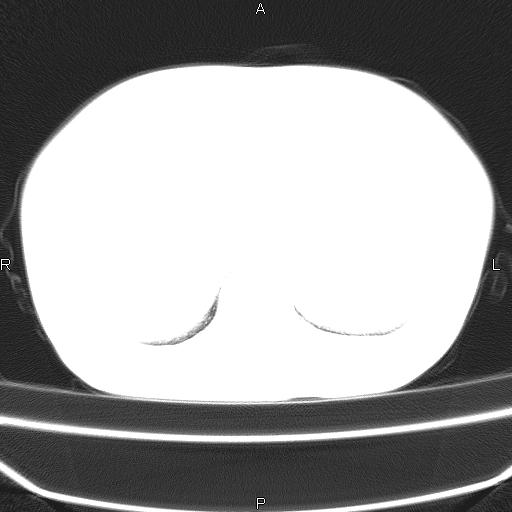

患者,女,66岁。健康体检胸部透视发现右上肺片状阴影。既往无不适,患者自诉三个月前曾有低热病史体温37.5左右一周。用药后缓解。至今无其它不适。请老师们指导指导。

考虑:右肺上叶周围型肺癌(分叶状肿块+砂粒状钙化+胸膜尾征)。

病灶见明显分叶、大小较大(大于3cm?),老年人,多考虑:肺癌,建议穿刺活检。

周围性肺癌可能性大,建议增强